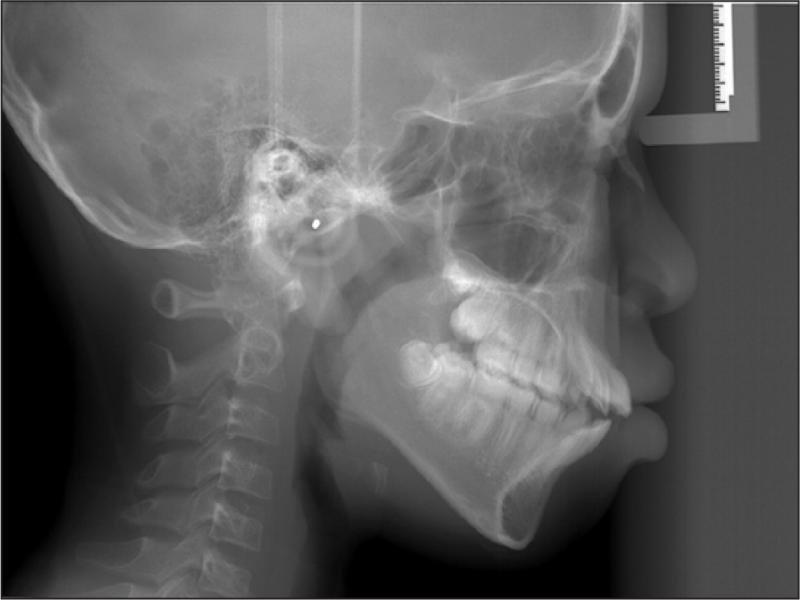

A 12-year-old African American male in good general health presented with the chief complaint of “I don’t like my upper front teeth”. An extra-oral examination revealed a convex soft tissue profile, an obtuse nasolabial angle, and lips that were protruded and incompetent. Upon intraoral examination, the patient had tooth staining, a retained deciduous upper left canine, a malformed upper right canine, a Class I molar relationship, spacing, an increased overjet and an anterior open bite (Figure 1). A radiographic examination revealed a congenitally missing upper left canine, an upper right permanent canine with a long root, an upper right first premolar with a short root, proclined and protruded upper and lower incisors and a high mandibular plane angle (Figures 2 and 3; Table I).

Lateral cephalogram taken at the initial visit (age 12 years, 0 months).